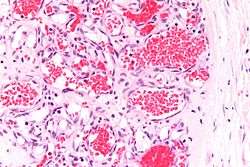

If the diagnosis is not clear based on physical exam and growth history (most often in deep hemangiomas with little cutaneous involvement), then either imaging or histopathology can help confirm the diagnosis.[28][4] On Doppler ultrasound an IH in the proliferative phase appears as a high flow soft-tissue mass usually without direct arteriovenous shunting. On MRI, IH show a well-circumscribed lesion with intermediate and increased signal intensity on T1 and T2-weighted sequences, respectively, and strong enhancement after gadolinium injections. There are fast flow vessels.[28] Tissue for diagnosis can be obtained via fine needle aspiration, skin biopsy, or excisional biopsy.[30] Under the microscope, hemangiomas are unencapsulated aggregates of closely packed, thin-walled capillaries, usually with endothelial lining. Blood-filled vessels are separated by scant connective tissue. Their lumens may be thrombosed and organized. Hemosiderin pigment deposition due to vessel rupture may be observed.[31] The GLUT-1 histochemical marker can be helpful in distinguishing IH from other items on the differential diagnosis, such as vascular malformations.[18]